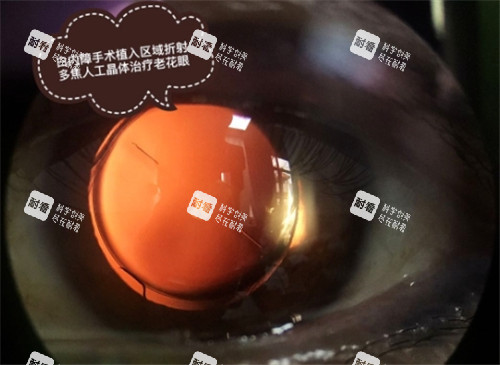

“沈阳普瑞眼科医院口碑好不好?”——答案藏在患者真实的笑容里!作为沈阳地区私立连锁眼科标杆,沈阳普瑞眼科凭借“技术硬、服务暖、环境优”三大核心优势,在近视矫正、白内障手术等领域收获了超95%的好评率。从术前细致检查到术后长期跟踪,从蔡司全飞秒4.0的更准操作到医生团队的个性化方案,患者们用“术后视力1.2”“10分钟完成白内障手术”“比子女还操心”等真实反馈,为这家医院打上了“靠谱”的标签。本文将